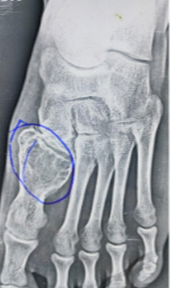

Case Series: Outcome of Giant Cell Tumor in Small Bones of the Foot

Yash Mehta , Rahul Parmar